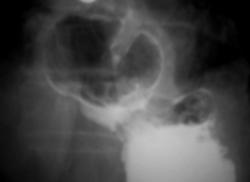

Пациент направлен на рентгенологическое исследование ЖКТР врачом терапевтом с диагнозом - "Хронический гастрит". В процессе проведения рентгенологического исследования выявлена грыжа пищеводного отверстия диафрагмы. Ваше мнение коллеги?

Картина фиксированной осевой (аксиальной) грыжи пищеводного отверстия диафрагмы, вероятно врожденный короткий пищевод (на снимке №11 виден его небольшой изгиб, но для полноценного пищевода этого недостаточно). Нарушение функции замыкающего механизма кардии. Насчет желудочно - пищеводного рефлюкса без скопии по одним снимкам неясно, во всяком случае явной перестройки складок нижних отделов пищевода нет.

Безусловно всей необходимой инфрмацией может располагать только врач проводивший конкретное исследование. Однако на всех представленных рентгенограммах нет снимка, где бы кардиальный отдел желудка был на своем законном месте - ниже купола диафрагмы, а это признак фиксированности грыжы. Хочу подчеркнуть, что неправомерно употребляемый часто нами, рентгенологами, термин "скользящая грыжа" есть не что иное - как синоним термина " аксиальная" (в отличие от параэзофагеальной), а вовсе не отражение состояния фиксированности (невправимости) или нет.